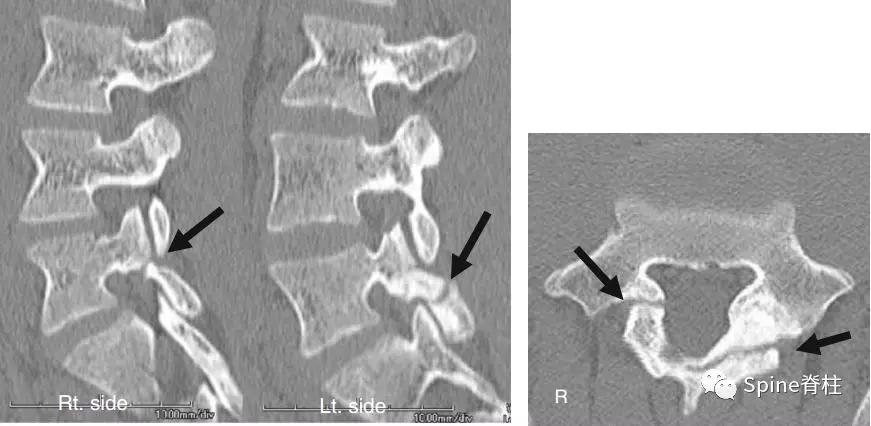

图:箭头所指为离断的椎体后缘

CT是诊断最有效的检查手段

- PARS的Takata分型:

图:A 型为分离部分含皮质骨,不伴椎体后方骨缺损(图A);B 型为分离部分较大,含皮质骨和松质骨,伴椎体后方较大骨缺损(图B);C 型为分离部分较小,含皮质骨和松质骨,伴椎体后方较小骨缺损(图C)。

由于对 腰椎椎体后缘离断症 (陈仲强)发生机理认识各异,有学者认为与青少年骺环未闭及运动创伤导致的椎体及骺环应力较大有关,也有学者认为是一种骨坏死,故命名尚未统一。